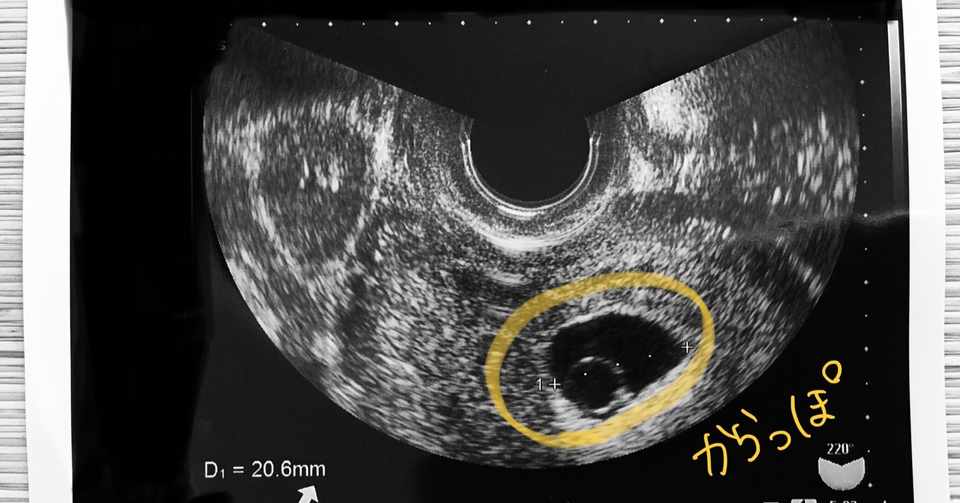

妊娠初期 胎嚢が小さいと言われてから心拍確認までの記録 よっちのパピルス帳

流産してしまったけど前向きになれた話 枯死卵って何 スンくじら Note